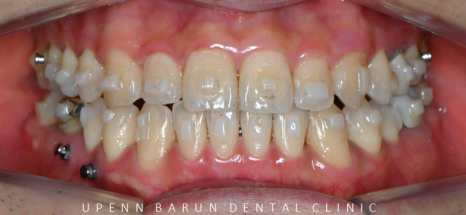

교정기간 21/4~24/3

잠실비발치인비절라인 교정후

반대교합이 개선되며 치열이 가지런해졌습니다.

반대교합으로 아래턱이 도드라져 보였던 이전과는 달리

반대교합이 개선되면서

옆모습의 입술과 턱라인이 정리된 모습입니다 :)

전체적으로 위,아랫니들이

제 위치를 찾으며 정리가 되었습니다!!

어금니들의 대이동이 끝이나고

클린체크의 예상대로 교정 마무리가 잘 되었어요!!

윗니와 아랫니 사이의 틈이 사라지고,

윗니를 덮고 있던 아랫니들이 제 위치를 찾으며 부정교합이 개선되었을 뿐만 아니라

정중앙선이 일치하도록 마무리 해드렸습니다 :)